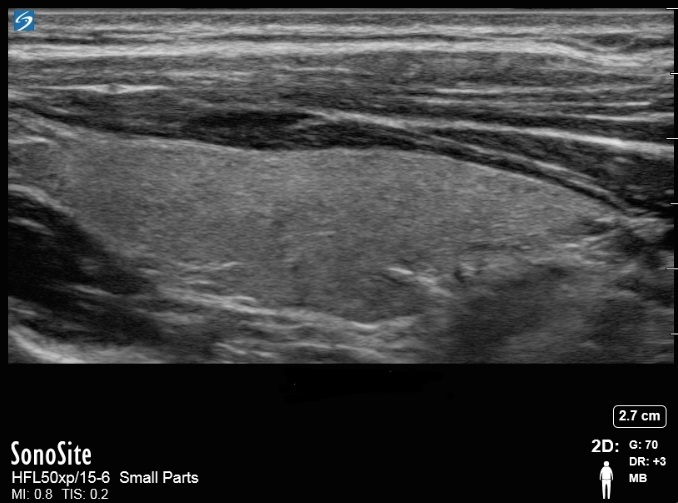

甲状腺サジタル像